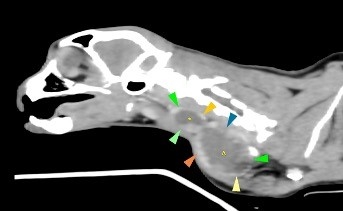

Diagnostic imaging specialist at Linnaeus-owned LVS Dr Ian Jones, immediately performed a CT scan which revealed the mass was multilobulated, meaning it had three parts, and was associated with the cat’s right thyroid gland.

Dr Jones said: “The great news for Mocky was that the mass was well encapsulated, meaning it could be removed with surgery and there were no signs of distant spread.

“Surgery was recommended before the mass got any bigger as it was already pushing on her wind pipe and osephagous, leading to her voice changes and difficulties in swallowing.”